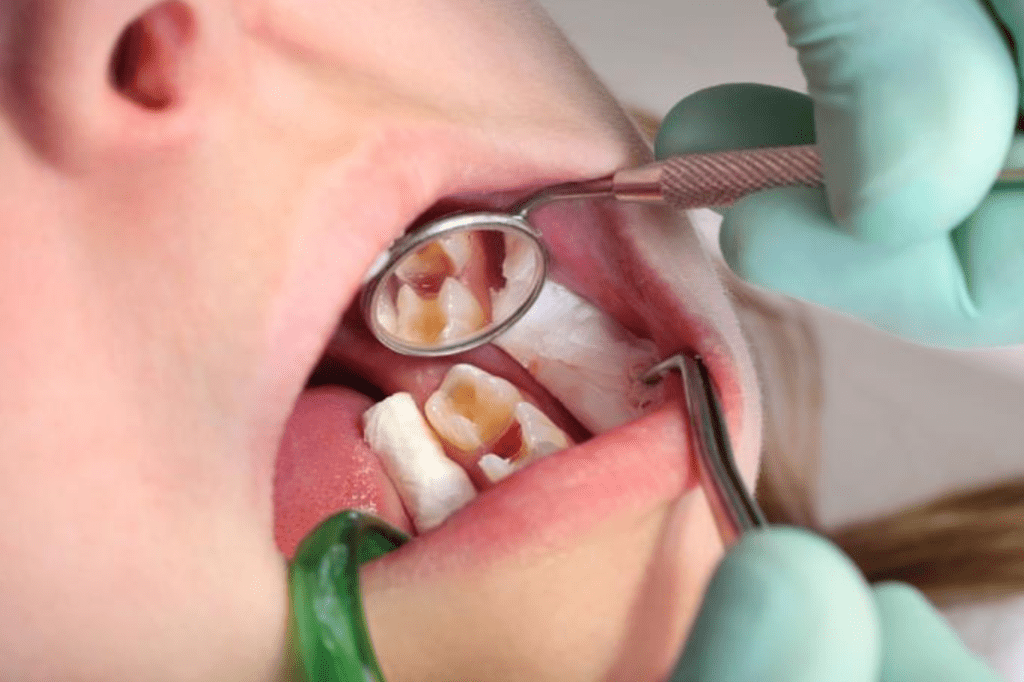

Để bạn hiểu một cách đơn giản thì điều trị tủy răng chính là việc tiến hành loại bỏ phần tủy đã bị viêm, hoặc chết. Đồng thời cũng thực hiện sử dụng vật liệu phù hợp để thay thế cho tủy răng tự nhiên của bạn, việc này gọi là trám bít ống tủy. Trước đây những chiếc răng có tủy bị bệnh đều được các nha sĩ chỉ định loại bỏ, tuy nhiên với công nghệ hiện nay thì không cần loại bỏ răng đó.

- Bước 4: Mở ống tủy, hút sạch những phần tủy đã bị viêm. Lúc này các bác sĩ sẽ dùng mũi khoan và những dụng cụ chuyên dụng để lấy những phần tủy hỏng ra khỏi buồng tủy răng.

- Bước 6: Trám bít cho phần tủy răng. Ở bước này bác sĩ sẽ sử dụng vật dụng nha khoa để trám bít lại hố đã lấy tủy tránh việc xâm nhập của vi khuẩn gây bệnh. Hoặc nếu như có kinh tế người bệnh cũng có thể lựa chọn điều trị tủy răng bọc sứ.